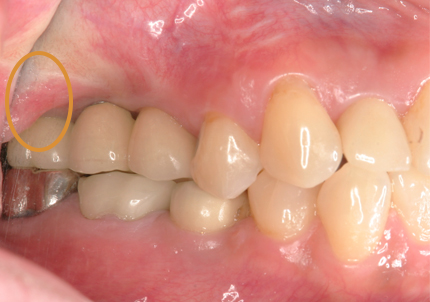

12.上顎補綴物装着(2009年5月)

13.下顎補綴治療開始(2016年1月9日)

16.下顎インプラント補綴治療終了(2017年4月8日)